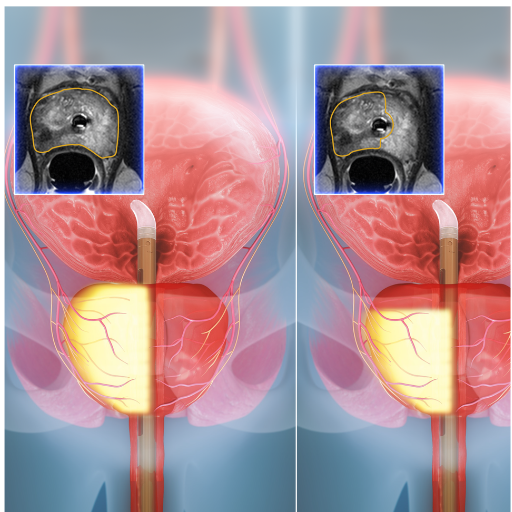

How TULSA-PROTM Works

A precise, four-step process guided by real-time MRI imaging

Real-time MRI provides clear views of the prostate and critical structures for precise planning.

Dr. Hong customizes treatment boundaries based on anatomy and areas to treat or spare.

The system delivers therapeutic ultrasound within prescribed boundaries while monitoring in real-time.